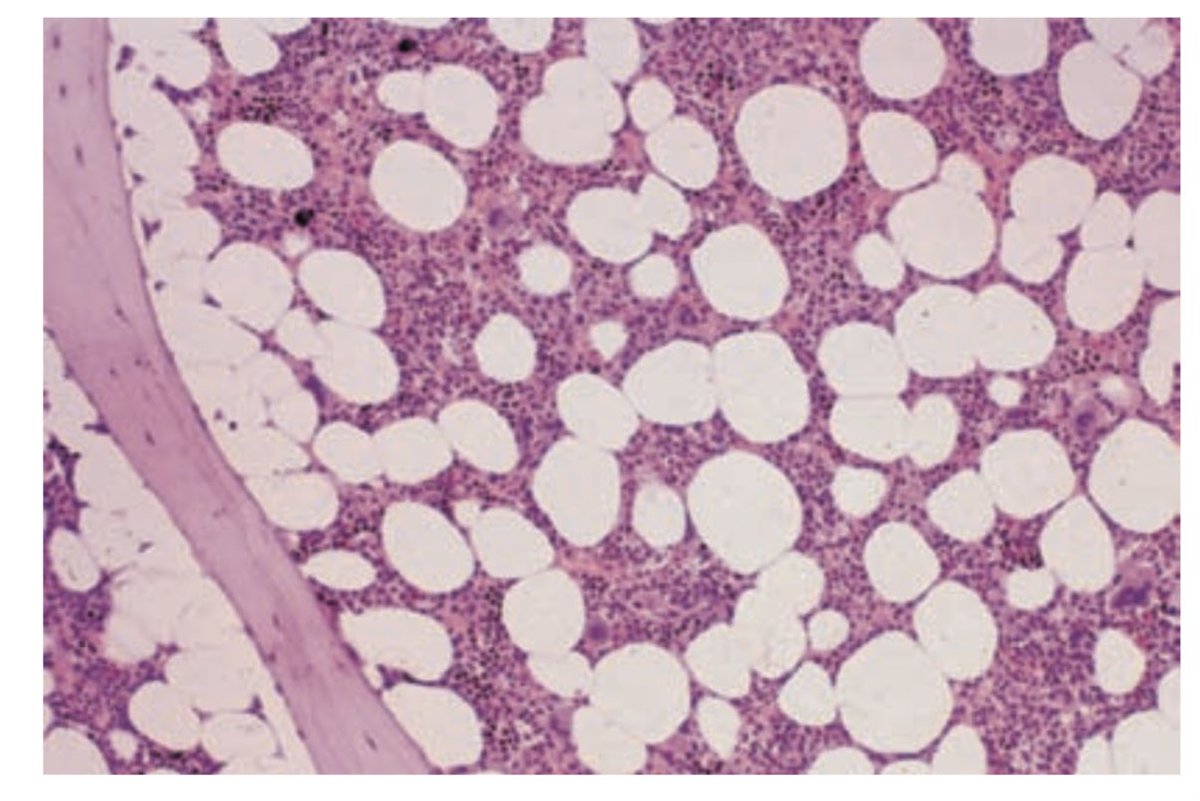

Infant الرضع تتكون في BM وكل العظام

Adult في BM واماكن معينه اهمها عظام القفص الصدري و عظمه الحوض والجمجمه